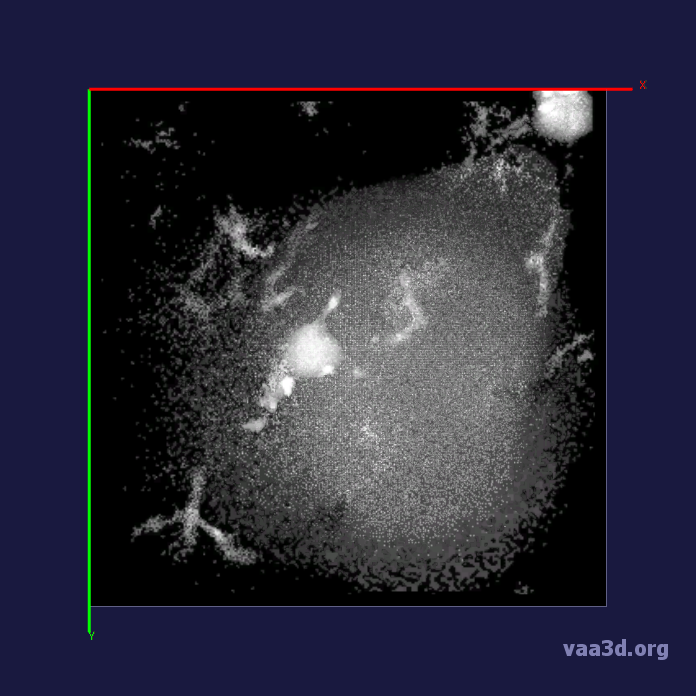

The 3D movies of microglia were imaged over 20 minutes with z-stacks taken at one minute intervals, containing single or multiple microglia per field of view. Some of the images were cropped from a larger field of view containing about 10 different cells and two images were imaged from a zoomed in view of one individual cell. The images ranged from a horizontal pixel width of .01 um and a vertical pixel width of .01 um to horizontal pixel width of .2 um and a vertical pixel width of .2 um. In the 3D images, there is variation in intensity contrast throughout the cell, non-structural noise, and fluorescence bleeding through z-stack due to the lengthy imaging technique which makes it difficult to visualize and process. The images were pre-processed using histogram equalization which increased the intensity throughout the cell but further increased noise in the background.

In our experiments, we compare the coupled TuFF-BFF microglia segmentation results with those given by L2S [21] and the Chan-Vese segmentation method [22]. The groundtruth in 3D was attained by manually tracing the object slice by slice from the z-stack. It must be noted that this was done by eye and could have some error. Figure 2 shows the visual comparison of the segmentation results for our dataset. Our result shown on the third column captures both the soma and processes. Figure 3 shows the Dice coefficient comparison of each segmentation method to the ground truth. Since the soma is much larger than the fine processes in the microglia, the processes have less volumetric impact on the similarity score. As explained in Section 1, segmenting the processes is important for quantifying the extension from the soma and its volume of surveillance. We use the Dice coefficient to quantitatively compare the ramification by taking the convex hull of the resulting segmentation. The Dice coefficient is a similarity measure that is computed using with where is the ground truth and is the compared image.

From Figure 4, the average Dice score for coupled TuFF-BFF was 0.77, compared to 0.53 for L2S [21] and .58 for Chan-Vese [22]. It must be noted that L2S required manual user initialization for each 2D image in the stack. While the Chan-Vese method has automatic seed selection, our coupled TuFF/BFF method was the only method that was a true 3D segmentation algorithm. L2S could not consistently capture the entire processes due to the intensity inhomogeneity throughout the object and background noise. The Chan-Vese segmentation could capture the extensions of the processes but did not work well with noise and attained false positives in the reconstruction. Since our method uses the tubular and blob information of the object to separate foreground and background, the segmentation only evolved within the object boundaries.